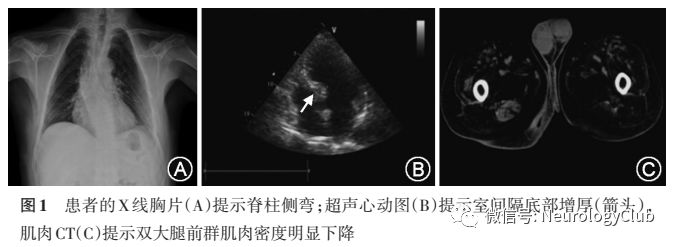

辅助检查:丙氨酸氨基转移酶35U/L(正常值9-60U/L)、天冬氨酸氨基转移酶125U/L(正常值15-45U/L)、总胆红素43.4μmol/L(正常值5-21μmol/L)、直接胆红素8.51μmol/L(正常值0.5-6.8μmol/L)、肌酐24.8mmol/L(正常值57-111mmol/L)、尿酸441.7μmol/L(正常值208-420μmol/L)、低密度脂蛋白胆固醇4.01mmol/L(正常值1.04-1.55mmol/L)、总胆固醇5.46mmol/L(正常值3.1-5.2mmol/L)。血清肌酸激酶862U/L(正常值38-174U/L),肌酸激酶同工酶37.6ng/ml(正常值0.6-6.3ng/ml)、血清肌红蛋白238.5ng/ml(正常值17.4-105ng/ml)。血、尿、便常规、血糖、糖化血红蛋白、甘油三酯、甲状腺功能、血气分析均无异常。胸片正位提示脊柱侧弯(图1A)。超声心动图提示房间隔中部菲薄,室间隔基底部肥厚约15mm(图1B)。腹部超声未见肝脾肿大。骨骼肌CT显示双侧臀部肌肉及大腿前群肌肉密度明显下降,左侧股二头肌较右侧重(图1C)。肌电图显示双正中神经运动传导速度及远端潜伏期正常,复合肌肉动作电位(CMAP)波幅降低;双侧尺神经、胫神经、腓神经运动传导速度、远端潜伏期以及CMAP波幅均正常,胸锁乳突肌、四肢多块肌肉、T11-10脊旁肌插入后均可见肌源性损害合并神经源性损害伴随大量肌强直放电(表1)。经患者本人知情同意后,行左侧肱二头肌活体组织检查(活检)及二代基因测序。

首都医科大学附属北京友谊医院神经内科代表:病例特点:(1)中年男性,隐匿起病,缓慢进展;(2)主要表现为对称性四肢近端肌力减退伴随肌肉萎缩;(3)体检可见咀嚼肌无力萎缩,四肢肌肉无力和萎缩,无肌肉强直现象,但存在脊柱侧弯;(4)家族中二级亲属为近亲结婚,无类似发病者;(5)辅助检查发现肌酸激酶升高,转氨酶升高,血清肌酐降低和血脂异常,肌电图肌源性损害,大量肌强直放电,肌肉CT提示腰部和大腿肌肉脂肪纤维化;(6)超声心动图提示室间隔基底段肥厚。

定位诊断:(1)骨骼肌,依据为四肢肌肉无力和萎缩,血清肌酸激酶升高,肌酐降低,肌电图提示肌源性损害以及骨骼肌CT;(2)心脏,依据有心慌症状和超声心动图提示室间隔基底段肥厚;(3)肝脏损害,依据为转氨酶升高。